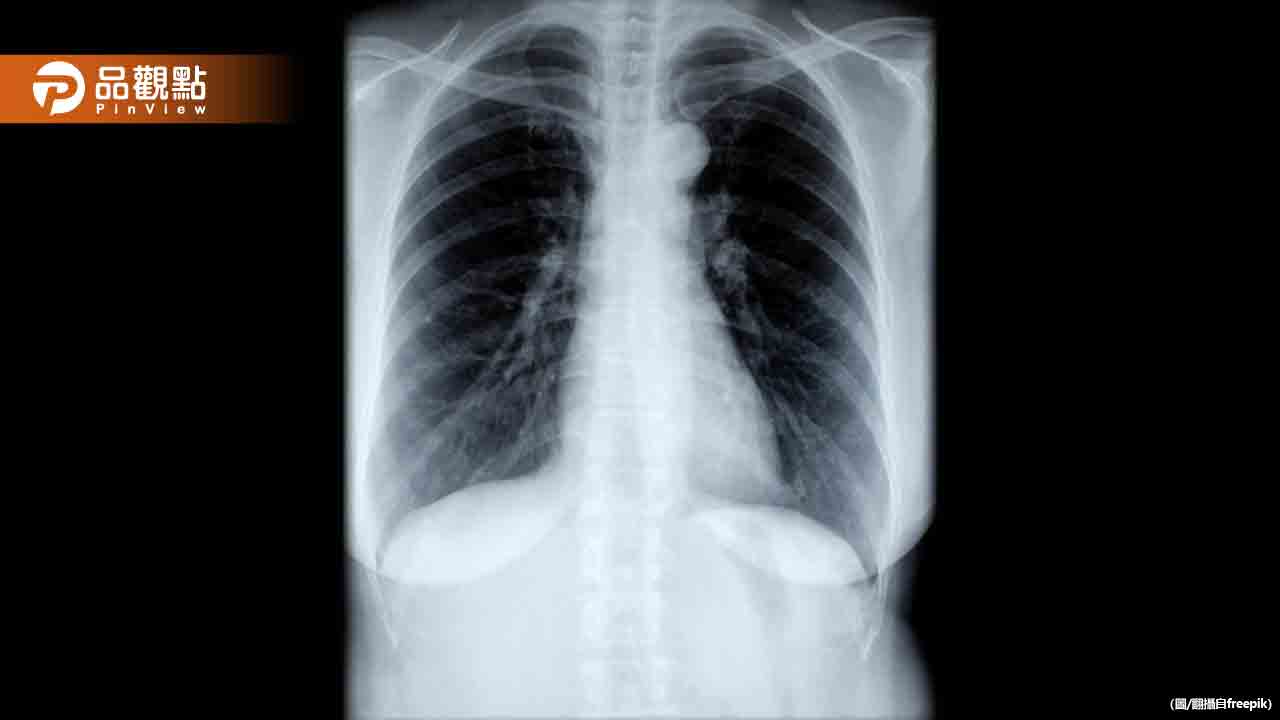

根據疾管署最新統計,上週新冠就診人次約1.9萬,較前一週上升。胸腔暨重症專科醫師黃軒指出,新冠病毒2025版「性格大改變」,現在改玩「潛行」模式,更容易人傳人。這次的病毒外表像感冒、腸胃炎,肺部卻可能默默出現「毛玻璃」。